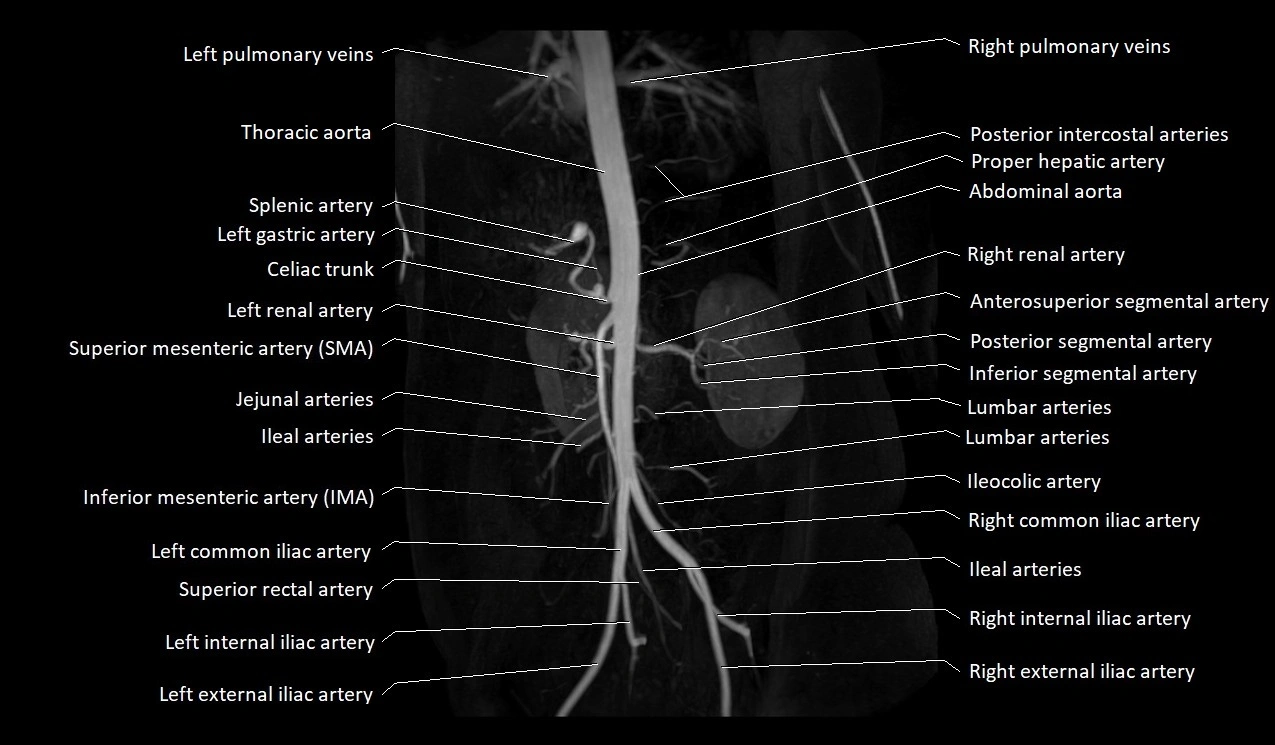

MRA Pelvis with Gadolinium:

-

Clearly delineates the origin, course, and anastomoses of the accessory obturator artery

Identifies connection with inferior epigastric artery, external iliac artery, or obturator artery

Excellent for detecting vascular variants prior to surgery

Useful in mapping pelvic vasculature in trauma, tumor embolization, or preoperative planning